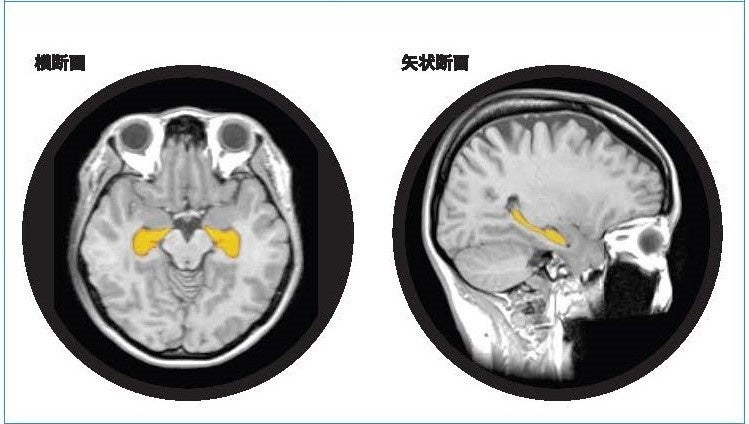

アルツハイマー型認知症は、顕著な脳萎縮を特徴としおり、脳の中でも海馬の萎縮は、20・30代から始まり、生活習慣要因によっては加齢性変化以上に萎縮が加速します。予防として健康なうちより生活習慣の改善をスタートすることがとても大切です。

「BrainSuite®」は、頭部MR画像のAI解析技術等を利用することで海馬の体積や萎縮程度を測定・評価し、同性・同世代と比較した脳の健康状態を可視化します。受検者にはBrainSuite®専用会員ページ「MyPage」が用意され、脳の健康維持・改善方法についてアドバイスを提供します。20代から80代の幅広い年齢層を対象に、「生涯健康脳」の実現を最新の脳医学の観点からサポートする検査サービスです。